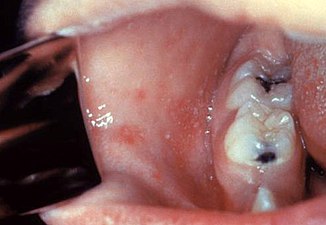

Koplik's spots seen inside the mouth are diagnostic for measles, but are temporary and therefore rarely seen.[21] Koplik spots are small white spots that are commonly seen on the inside of the cheeks opposite the molars.[20] They appear as "grains of salt on a reddish background."[23] Recognizing these spots before a person reaches their maximum infectiousness can help reduce the spread of the disease.[24]

Koplik's spots on the third pre-eruptive day

Koplik's spots on the day of measles rash.